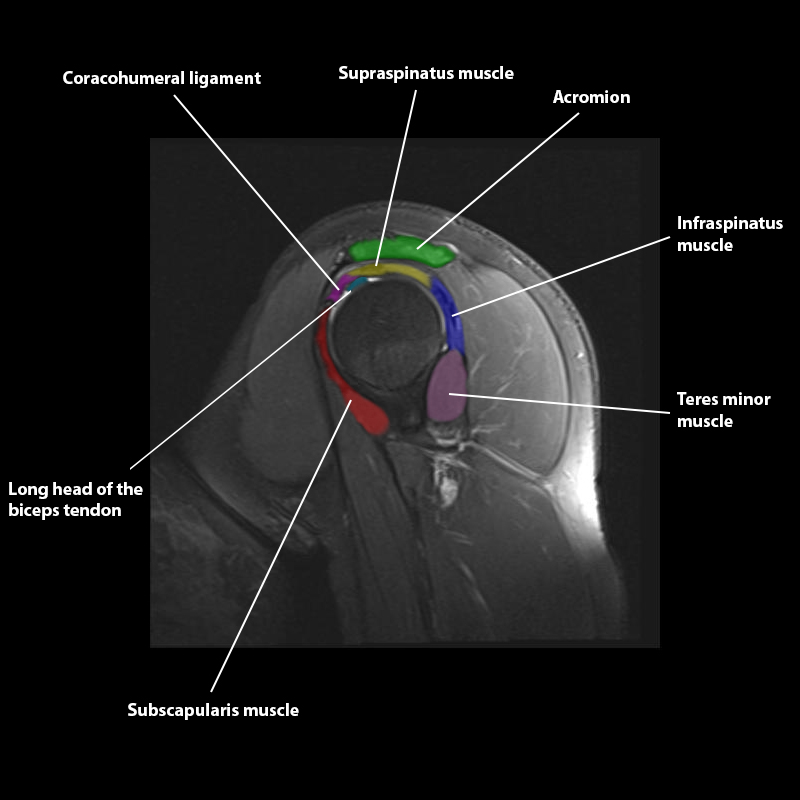

Shoulder MRI Anatomy